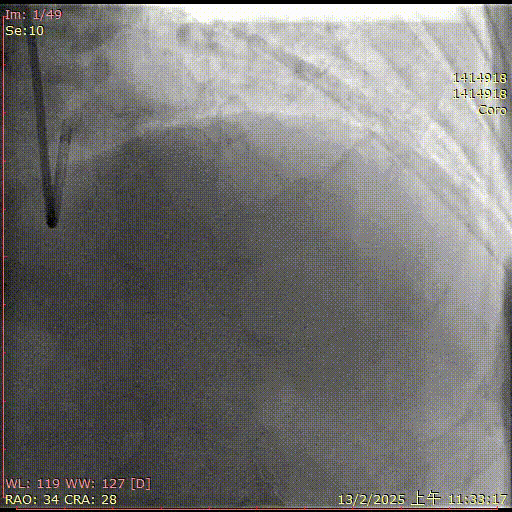

术前造影

术后造影